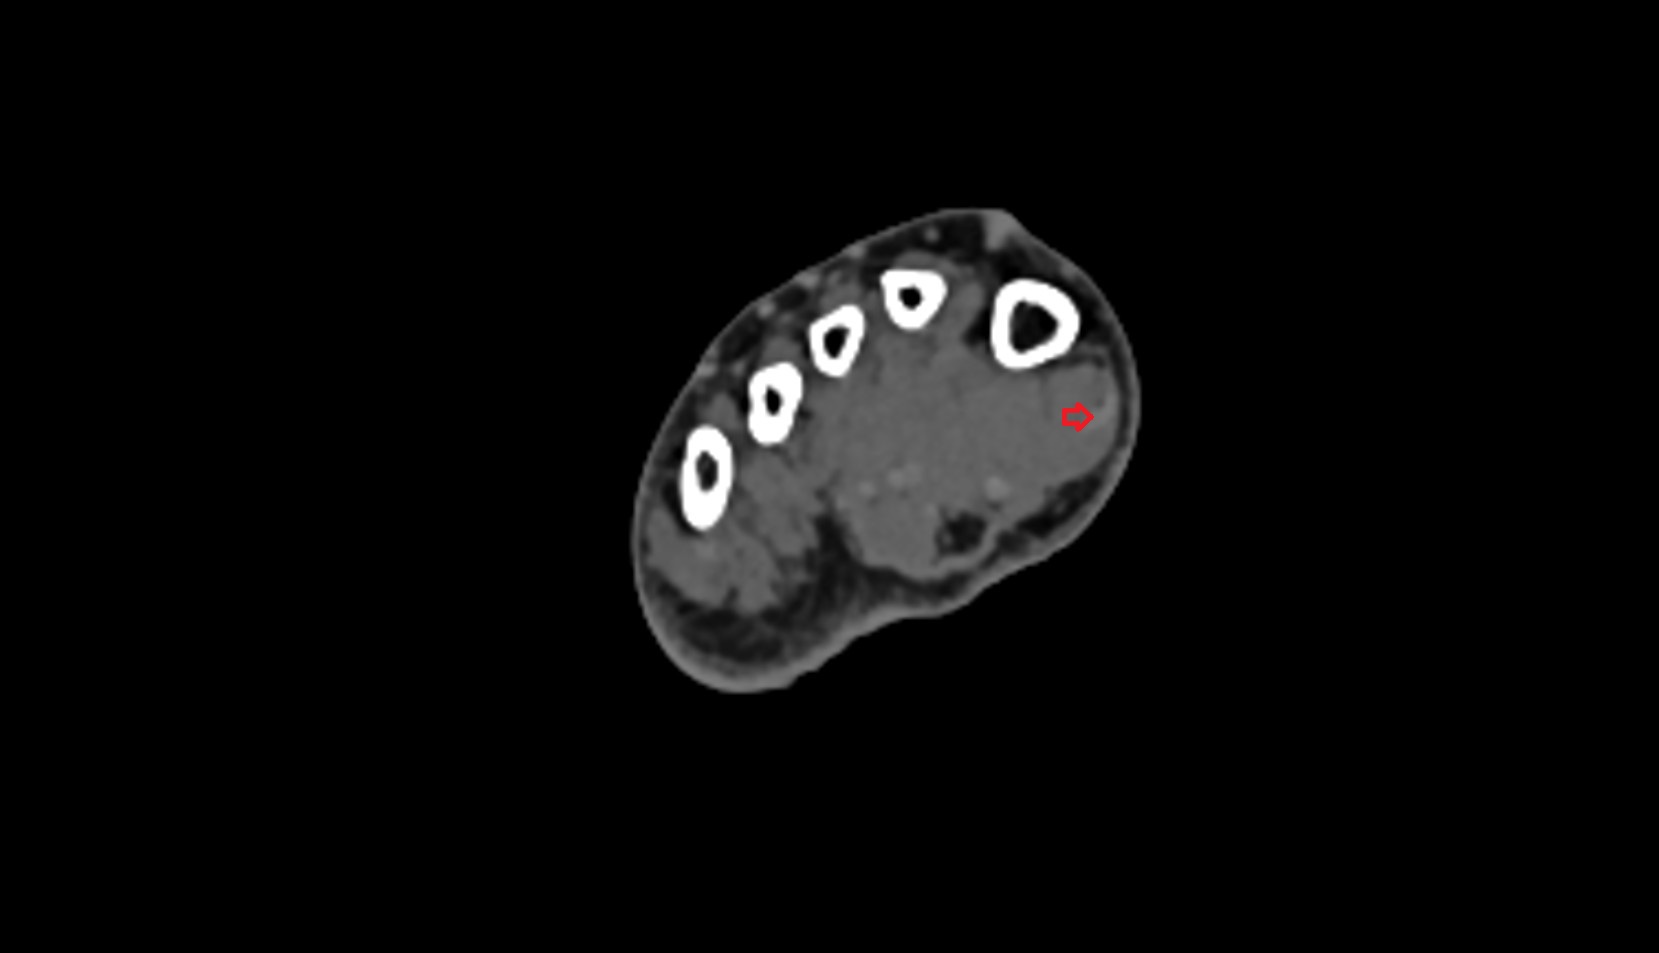

- Calcaneus

- Talus

- Body of talus

- Neck of talus

- Sustentaculum tali

- Talocalcaneal joint